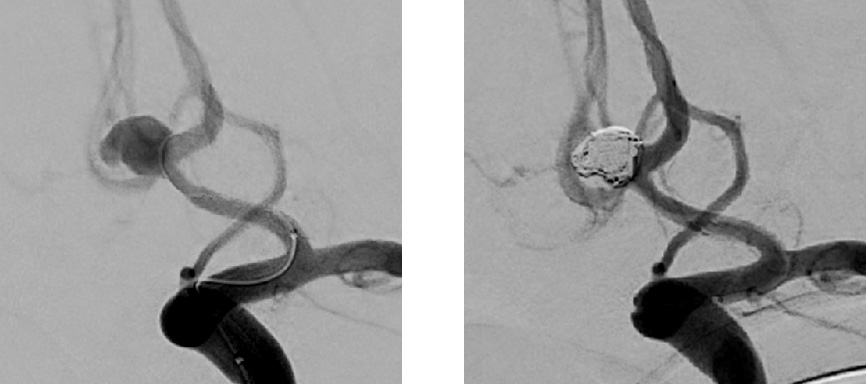

【脳動脈瘤コイル塞栓術】

脳ドックや頭痛・めまいの検査で偶然に発見された脳動脈瘤(未破裂脳動脈瘤)や、くも膜下出血を発症されて診断がついた脳動脈瘤(破裂脳動脈瘤)に対して、検討される手術です。

基本的に全身麻酔で行います。

片方あるいは両方の足の付け根から径2~3mmのカテーテルを挿入し、最終的には径0.5~1mmの非常に細いカテーテルを動脈瘤の中に留置し、プラチナの糸(コイル)を動脈瘤の中に充填して内部から動脈瘤へ血流が入らないようにする治療です。

(左:留置前 右:留置後)

コイルが動脈瘤からはみ出さないように(正常な血管に逸脱しないように)、動脈瘤の入り口を一時的に風船を膨らませることでガードしたり、ステントと呼ばれる網目状の金属の筒でカバーすることもあります。

この治療で生じる傷は足の付け根に数ミリ程度のため、開頭手術と比較して侵襲が少ないという利点がありますが、動脈硬化や加齢性変化で血管の屈曲が非常に強い場合には困難なことがあります。

動脈瘤の治療法はコイル塞栓術のほかに、開頭手術による脳動脈瘤頸部クリッピング術があり、それぞれが得意とする動脈瘤があります。患者さんの動脈瘤に適した、また全身状態などを総合的に検討し、安全で確実な治療方針をご提供できるよう努めております。